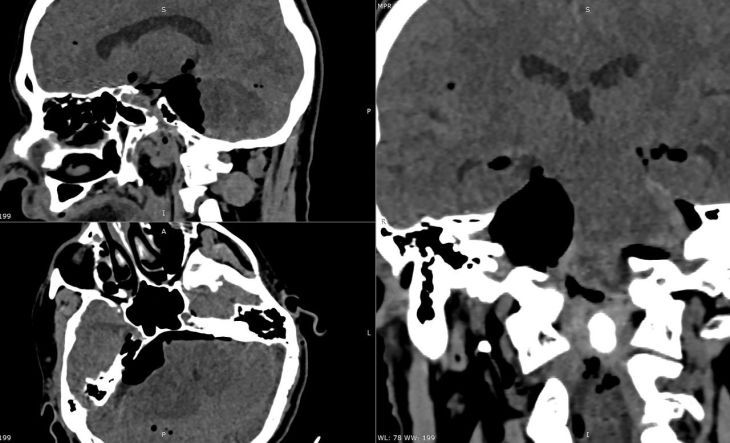

Опухоль, образовавшуюся возле жизненно важных структур мозга пациента, удалили специалисты Федерального медико-биологического агентства.Новообразование занимало четверть самого глубокого отдела внутреннего основания черепа. Без...

Она выросла в крошечном пространстве у основания черепа, где буквально «упакованы» жизненно важные структуры: нервы, отвечающие за мимику, зрение, глотание, дыхание, а также сам ствол мозга — центр управления жизнью.Опухоль размером с орех уже...